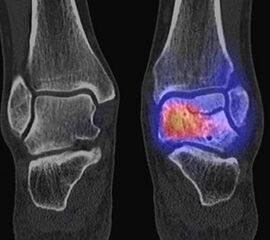

Abbildung 1.8.a und b: Akute Arthritis bei bekannter Gicht in beiden OSG: links die Früh-/Weichteilphase; rechts die Mineralisations­phase. Deutliche, entzündlich bedingte Mehranreicherungen in der Früh-/Weichteilphase. In der Mineralisation­sphase erkennt man die entzündliche Mitreaktion der subchondralen Gelenkabschnitte.

Zum Lesen der Bildbeschreibung und zur Vollansicht bitte das Bild anklicken. Bild: H. C. Rischke

Abbildung 1.8.c - e: Akute Arthritis in beiden OSG, rechts > links. Im SPECT/CT erkennt man die Mitreaktion der subchondralen Gelenkabschnitte. Die Arthritis ist so akut, dass (noch) keine ossären morphologischen Veränderungen im CT abgrenzbar sind.

Zum Lesen der Bildbeschreibung und zur Vollansicht bitte die Bilder anklicken. Bilder: H. C. Rischke